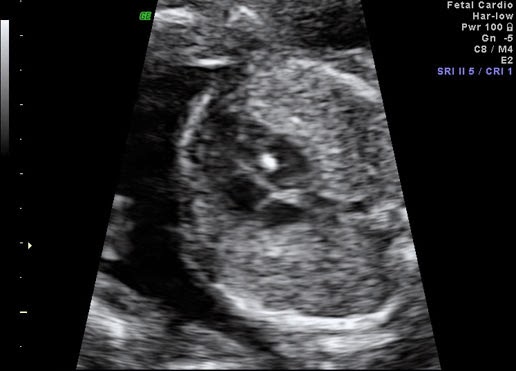

Bebeğin kalbinde beyaz leke. Sağlıklı bebeklerde de görülebilen kalpteki beyaz lekeler zeka geriliği olan bebeklerde daha çok görülmektedir. Hamilelikte görülen bu rahatsızlık sonucu nedir bebeklerin gelişimini etkiler mi. Haftaları arasında yapılan detaylı ultrason incelemesi ile fark edilir. Gebeliğin özellikle 18 23 hafta detaylı ultrasonografik incelemesi sırasında saptanabilen bebek kalbinde parlak leke ekojen odak parlaklık veya kireçlenme ismi ile halk arasında bilinen durumun tıbbi ismi.

Halk arasında bebeğin kalbinde kireçlenme olarak bilinen bu durumun tıbbi ismi fetal kalpte hiperekojen odak olarak geçer. Fetal kalpte ekojen hiperekojen odak tır. Bebeğin kalbinde göze çarpan beyaz leke parlaklık genelde gebeliğin son iki ayında kendiliğinden geçmektedir. Hamilelikte bebeğin kalbinde beyaz leke bulunması aileler için hiç beklenmedik bir anda gelen endişe ve üzüntüye yol açan bir durumdur.

Bebeğin kalbinde beyaz leke görünmesi. Merhaba 17 haftalık gebeyim dün kontrolümde drum bebeğin kalbinde beyaz leke gördü 2li testim normal sizce ayrıntılı usg yaptırmalı mıyım down sendromuyla alakası nedir çok korkuyorum lütfen yardımcı olun. Bebeğin kalbinde beyaz leke olması veya parlaklık görülmesi durumunda yapılması gerekenler bulunmaktadır. Kalpte parlak beyaz bir oluşum şeklinde görülür.